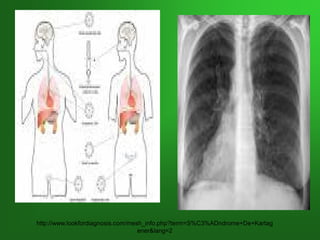

IRA BAJA: 8. SITUS INVERSUSIRA BAJA: 8. SITUS INVERSUS

YY SdSd DE KARTAGENERDE KARTAGENER

Trastorno autosómico recesivo caracterizado por

DEXTROCARDIA, INFERTILIDAD Y SINUSITIS

Por mutaciones en los genes de DINEINA que

codifican proteínas de movilidad componentes de

las colas de los espermatozoides y de los cilios

respiratorios y tubáricos.

Llamada también:Discinesia Ciliar Primaria o

Tríada de Kartagener

SITUS INVERSUSSITUS INVERSUS

http://www.lookfordiagnosis.com/mesh_info.php?term=S%C3%ADndrome+De+Kartag

ener&lang=2